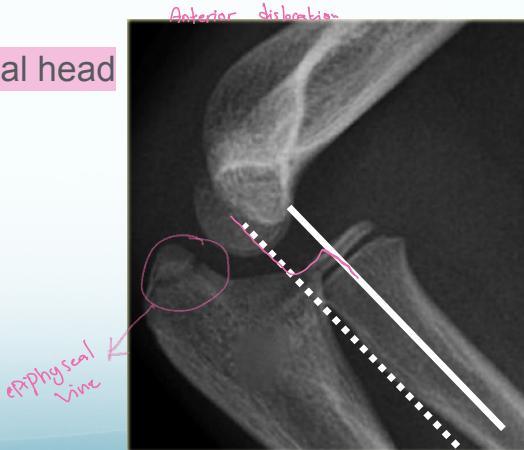

Lateral Condyle - Humerus

- Mostly cartilaginous

- Intra-articular fracture

- Fracture easily missed

- Displacement not appreciated/underestimated

- Needs fixation even if undisplaced

- Treatment: reduction, K-wire, slab

- If not fixed, may displace